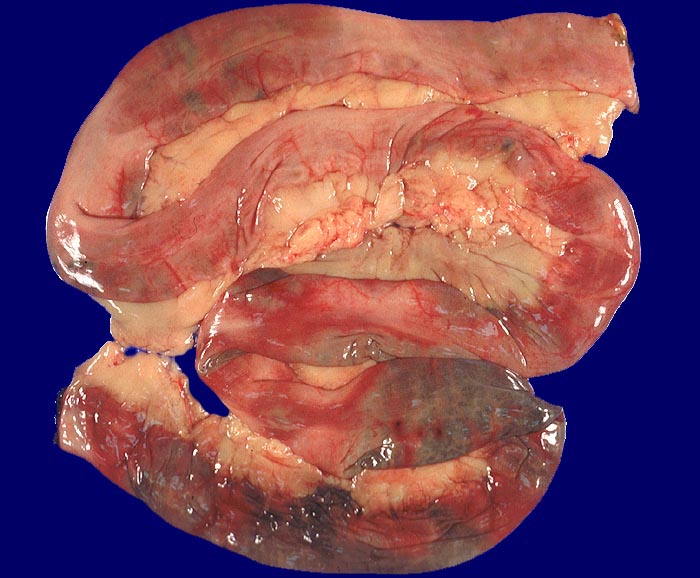

AP/ Mesenterialinfarkt

Mesenterialinfarkt

vaskulär / Durchblutungsstörung

Darm, Anus

Dünndarm

Makroskopie

Pathologischer Befund